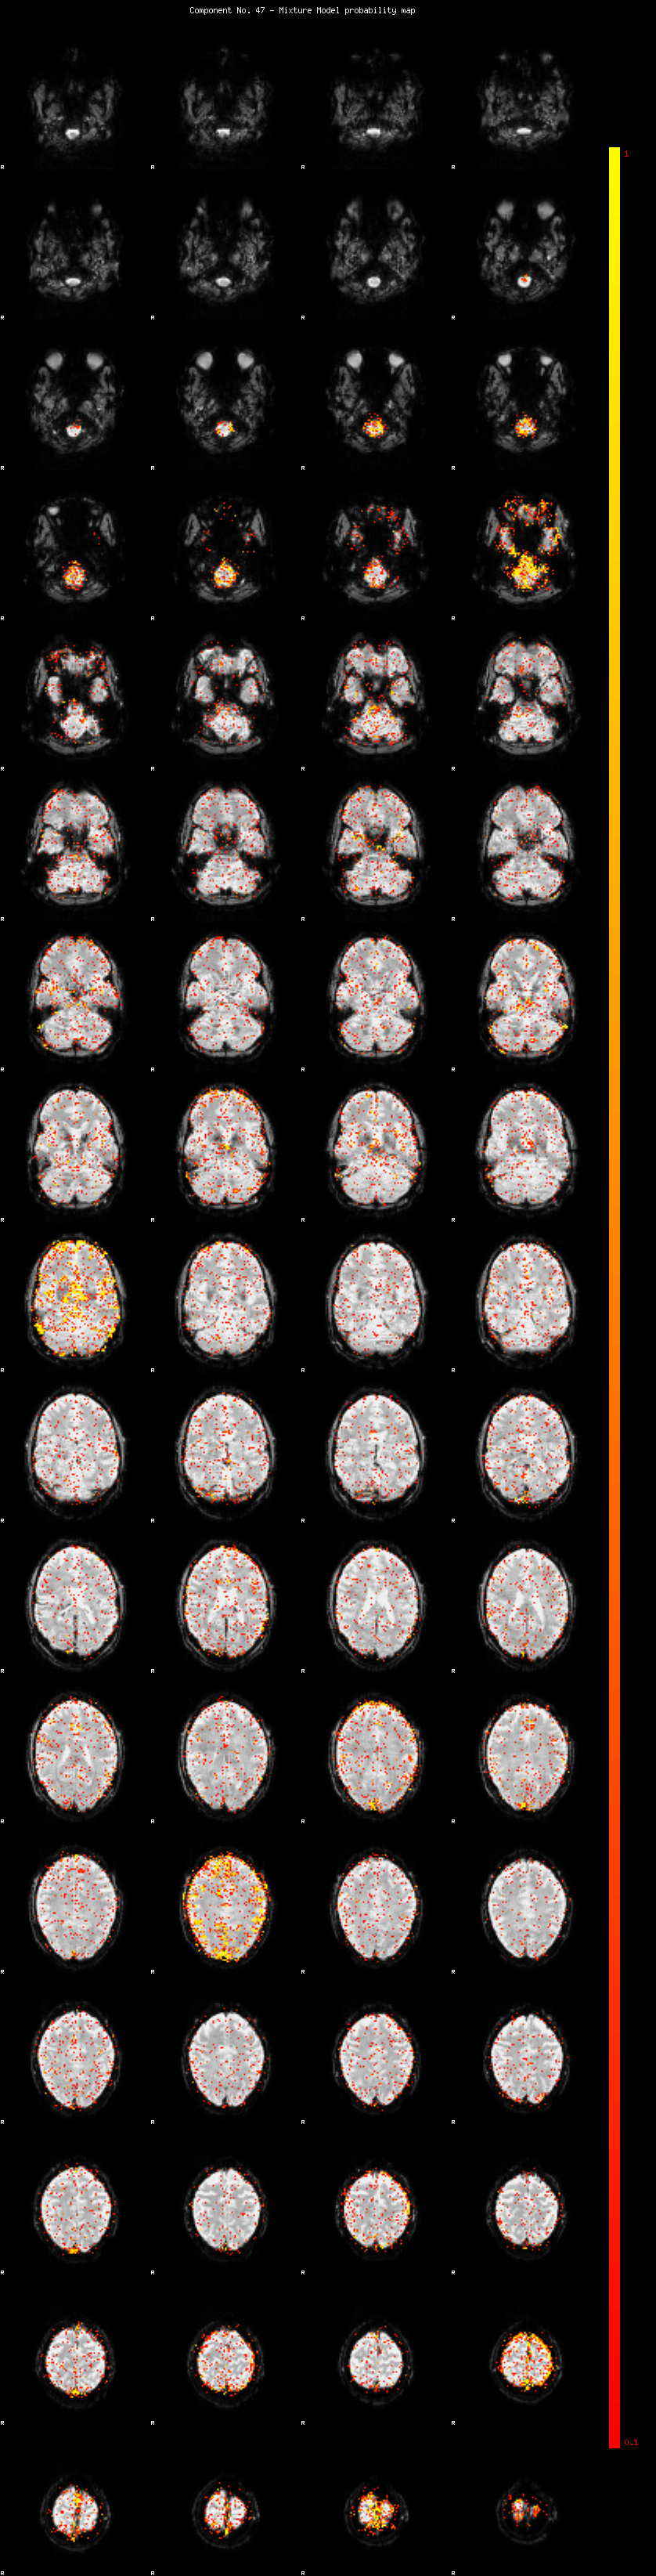

IC_47 Mixture Model fit

Means : -0.000000 2.661223 -2.345617

Vars : 1.000000 2.683451 1.629799

Prop. : 0.948770 0.024354 0.026876